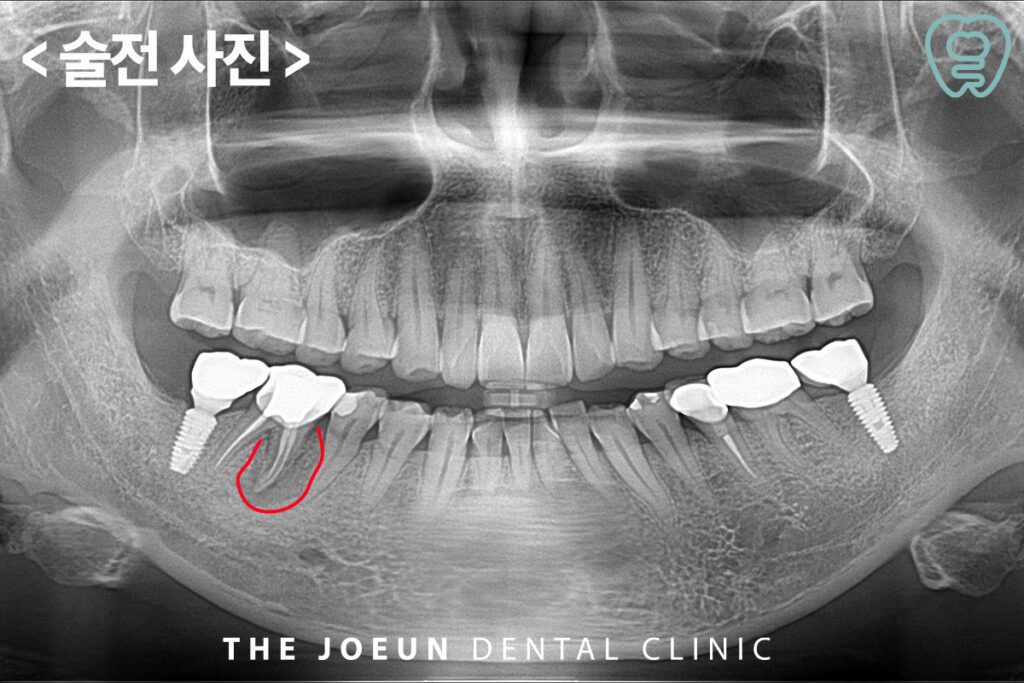

오늘은 오래 된 치아 뿌리의 염증으로 인해 자연치를 발치하고 뼈이식 후 6개월 만에 임플란트를 식립하여 완성하신 환자분을 소개해 드리도록 하겠습니다. 환자분께서는 오랜만에 구강 검진 차 내원하셨다가 우연히 왼쪽 아래 어금니의 커다란 염증을 알게 되셨는데요. CT 상에서도 확연하게 뿌리 주위를 감싸고 있는 까만 염증 부분을 확인할 수 있었습니다. 평상시 불편을 느낄만한 큰 통증이 없었기 때문에 전혀 모르고 계셨지만 이미 잇몸뼈를 많이 녹인 상태로 발치를 하더라도 바로 임플란트 진행이 불가능할 것이라고 판단되어 뼈이식 후 충분한 기간을 기다려준 뒤 임플란트 식립을 진행하기로 하였습니다.

먼저 염증이 심한 치아를 발치하고 뼈이식을 진행하였습니다.